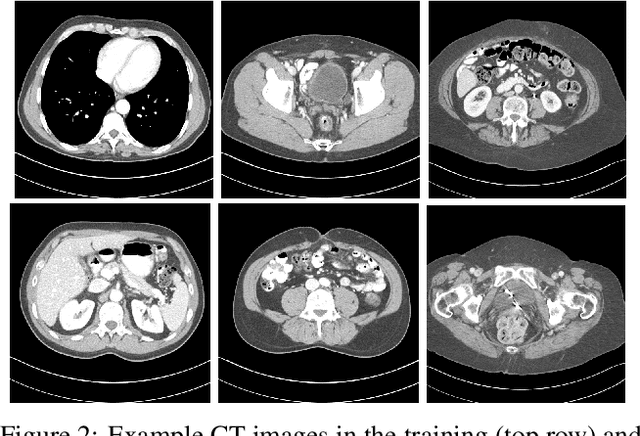

Abstract:Recent years have witnessed growing interest in machine learning-based models and techniques for low-dose X-ray CT (LDCT) imaging tasks. The methods can typically be categorized into supervised learning methods and unsupervised or model-based learning methods. Supervised learning methods have recently shown success in image restoration tasks. However, they often rely on large training sets. Model-based learning methods such as dictionary or transform learning do not require large or paired training sets and often have good generalization properties, since they learn general properties of CT image sets. Recent works have shown the promising reconstruction performance of methods such as PWLS-ULTRA that rely on clustering the underlying (reconstructed) image patches into a learned union of transforms. In this paper, we propose a new Supervised-UnsuPERvised (SUPER) reconstruction framework for LDCT image reconstruction that combines the benefits of supervised learning methods and (unsupervised) transform learning-based methods such as PWLS-ULTRA that involve highly image-adaptive clustering. The SUPER model consists of several layers, each of which includes a deep network learned in a supervised manner and an unsupervised iterative method that involves image-adaptive components. The SUPER reconstruction algorithms are learned in a greedy manner from training data. The proposed SUPER learning methods dramatically outperform both the constituent supervised learning-based networks and iterative algorithms for LDCT, and use much fewer iterations in the iterative reconstruction modules.